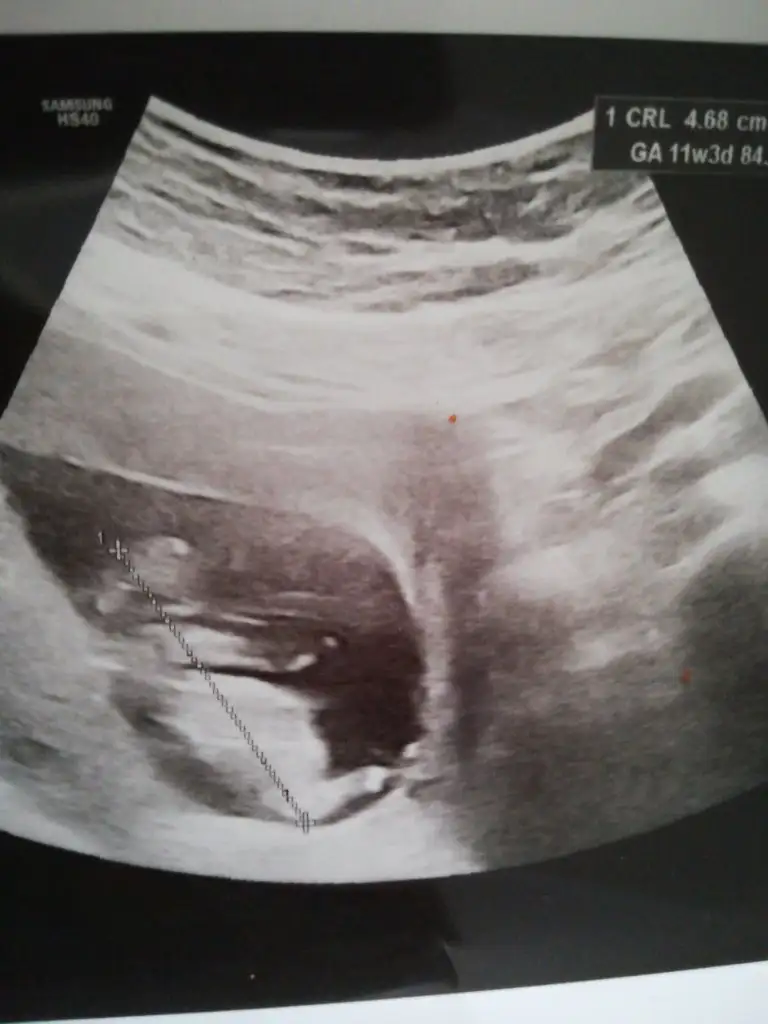

Buda 17 haftalik yeni hala ogrenmedin mi dersen ogrenemedimNet olmamakla birlikte kız sanki başka usg varmı 11 yada 12 hafta

12 haftalık başka yok maalesef haftaya gidecek testin sonucunu almayaKaç haftalık usg sanki erkek gibi başka usg varsa 11 yada 12 hafta tahmin ederiz